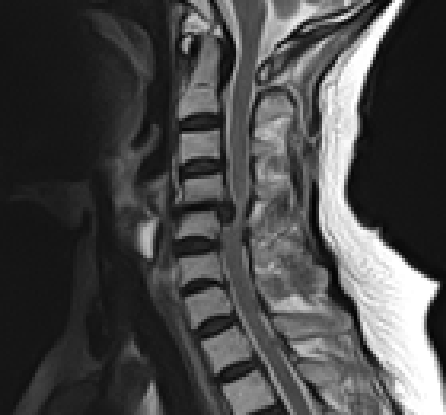

頚椎も腰椎同様に椎骨と椎骨の間に椎間板が存在し、脊柱に可動性を持たせながらクッションとしての役割も担っており、加齢等により周囲の線維輪に亀裂が入り内容物が脱出する椎間板ヘルニアになることがあります

症状はヘルニアの突出方向によって異なりますが、脊髄自体や脊髄から分岐した神経根(神経の枝)を圧迫することにより、片側の頚部から肩および肩甲骨・腕などの痛みやしびれを生じ、筋力低下を呈することもあります。一方、中央に大きく突出した場合には脊髄自体を圧迫することにより、手指の細かな運動がしづらい、歩行障害や膀胱直腸障害(頻尿、尿閉、尿失禁など)などの症状が出現します。保存療法で強い痛みやしびれが改善されない場合や、脊髄や神経根の圧迫による神経障害が出現した場合には頚椎椎弓形成術などの手術を要する場合もあります。